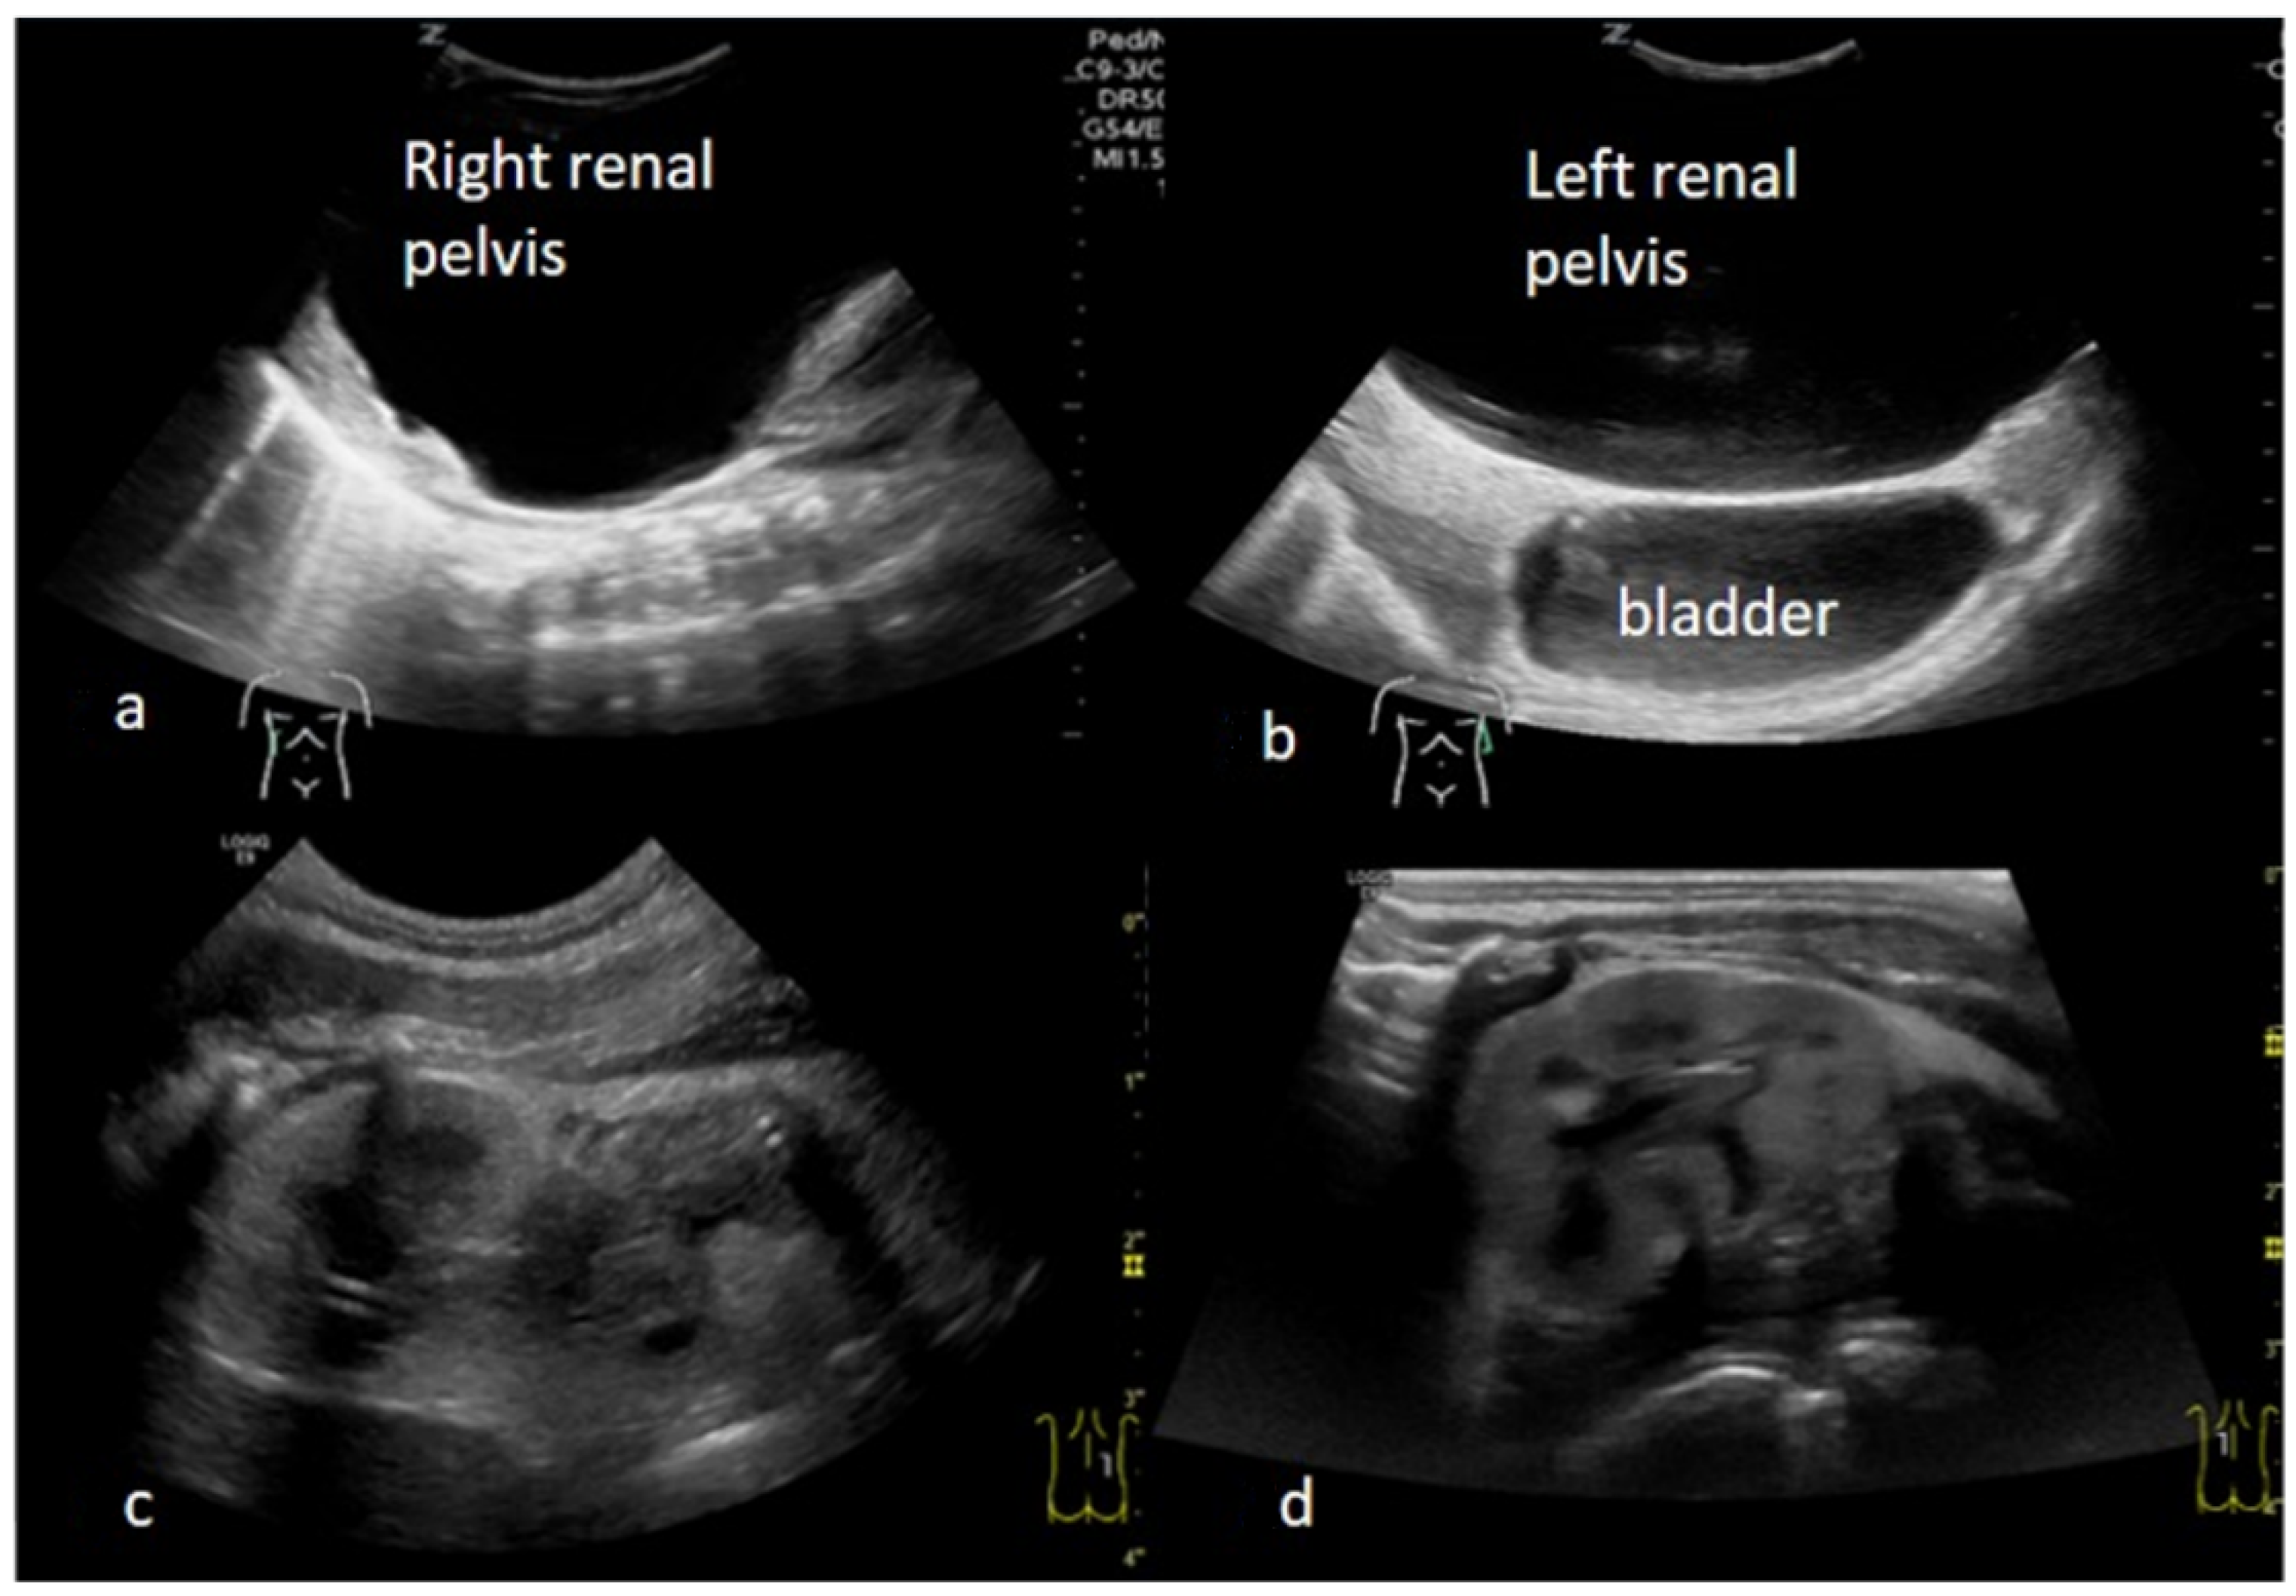

2. Case Presentation